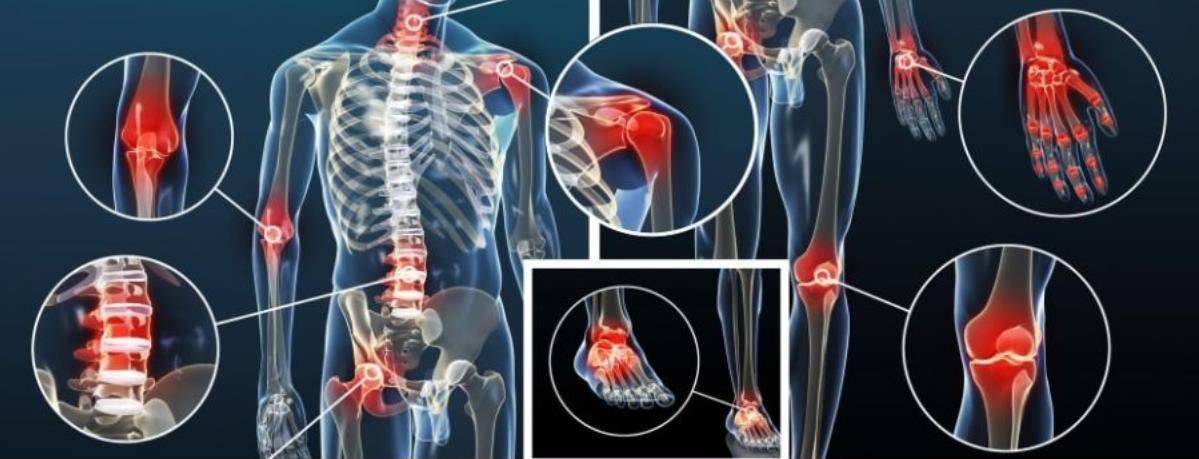

На рисунке здоровые и пораженные артрозом суставы

На рисунке здоровые и пораженные артрозом суставы